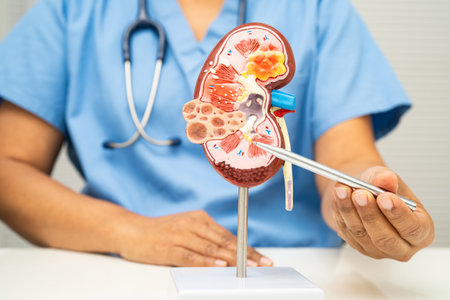

Kidney disease, Chronic kidney disease ckd, Doctor hold human model to treat and study in hospital.

Chronic kidney disease, doctor with model for treatment urinary system, urology, Estimated glomerular filtration rate eGFR.

Chronic kidney disease, doctor with model for treatment urinary system, urology, Estimated glomerular filtration rate eGFR.

Kidney disease, Chronic kidney disease ckd, Doctor hold human model to treat and study in hospital.

Kidney disease, Chronic kidney disease ckd, Doctor hold human model.

Chronic kidney disease, doctor holding model for treatment urinary system, urology, Estimated glomerular filtration rate eGFR.

Chronic kidney disease, doctor with model for treatment urinary system, urology, Estimated glomerular filtration rate eGFR.

Chronic kidney disease, Asian woman with model for treatment urinary system, urology, Estimated glomerular filtration rate eGFR.

Kidney disease, Chronic kidney disease ckd, Doctor hold human model to treat and study in hospital.

Chronic kidney disease, doctor holding model for treatment urinary system, urology, Estimated glomerular filtration rate eGFR.

Chronic kidney disease, doctor holding model for treatment urinary system, urology, Estimated glomerular filtration rate eGFR.

Kidney disease, Chronic kidney disease ckd, Doctor with human model to study and treat in hospital.